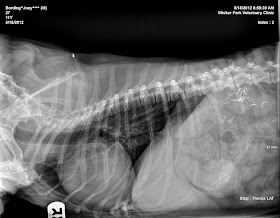

We're always fascinated with the inner workings of a Dachshund, and have featured x-rays of Joey and our dear departed Maggie several times over the years.  We recently went to the vet to have a look at Joey's heart.  With all the medical conditions that he has, he also has had a heart murmur his entire life, and it has progressed to about a grade 3.  Heart murmurs are common in small dogs such as Dachshunds, and they worsen as the dogs get older, eventually leading to CHF, or congestive heart failure.  If Joey were to start showing signs of exercise intolerance or "coughing," it will be time to start him on some cardiac meds.  Thankfully, he's not showing any of these symptoms yet, but with the long-standing condition, it was prudent to have a look inside.

We were happy to find that things look pretty good.  You can see his heart in the above photo, center left, and it does not appear to be enlarged.  That's his lungs to the right of the heart, and there doesn't appear to be any fluid buildup, so that's positive as well.

Our wonderful veterinarian and hero, Dr. Cohen at Wicker Park Veterinary Clinic, had a good laugh when he noticed all of Joey's "hardware."  If you look in the upper right, you can see all the surgical staples inside him from his previous bi-lateral adrenalectomy and spleenectomy, and it took a minute to realize what all the foreign bodies were!  Hopefully Joey won't have to go through any metal detectors any time soon.  You can see another staple in the belly-view photo below near one of his ribs.